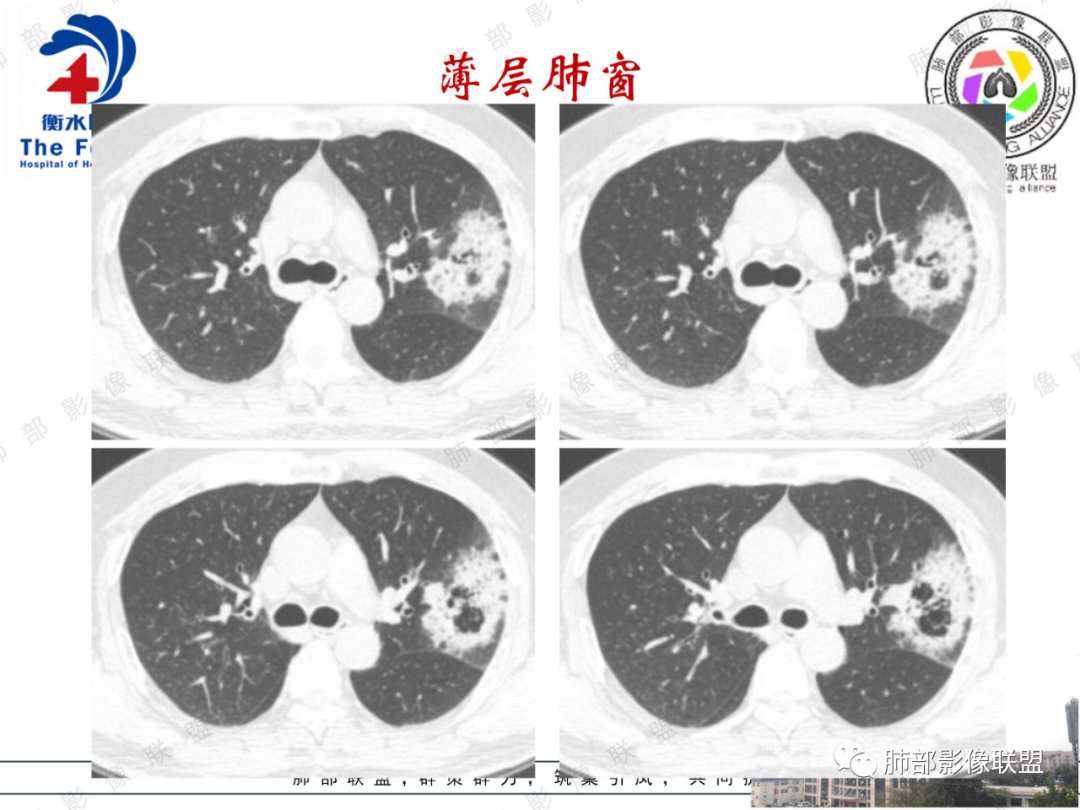

左肺上叶实变影,其内可见多个簇状空洞,大小不一,其内可见分割,多个堆积而成,内外壁光滑,空洞边缘毛糙,可见长索条牵拉胸膜,收缩为主,周围伴有磨玻璃影,随访两个月空洞依旧还在,不知道症状有无减轻,临床培养肺克(是否为致病菌?)有糖尿病,慢性起病,临床炎性指标正常,考虑:1肺癌(假大空,炎性症状不明显都支持)2:真菌(毛霉,无咯血,曲霉)3:GPA(单发少见)4:结核(形态太单一,周围无播散灶)

瘤肺界面清晰,边缘短毛,其内见假大空及空泡,胸膜下多发线条影(胸膜凹陷还是反应性增厚),治疗后两个月没有变化,真菌感染?肺腺癌?

左肺上叶肿块,内可见假大空,多发分隔,肿块膨隆、分叶,边缘毛糙,可见长索条,抗炎治疗无效,首先考虑肿瘤,腺癌可能大

中老年男性患者,亚急性起病,咳嗽、咳痰2月,无发热,有糖尿病病史,血炎症指标不高,胸部CT:左肺尖后段斑片状病灶,内部多发小空洞,周边磨玻璃影,抗感染治疗症状好转,2月后复查空洞似乎有增大,考虑恶性,肺炎性肺癌可能,鉴别炎性病变

影像所见:左肺上叶尖后段团片状高密度影,边界清楚,其内密度不均,中心呈多发低密度影,与支气管关系显示不清。

中年男性,糖尿病,左肺上叶团片状高密度影,反晕,边缘毛糙,晕中毛刺,中心分隔,其内可见支气管影,抗炎效果差,2月复查病灶增大,中心密度减低,似空洞形成,首先考虑真菌感染,腺癌待排

中老年男性,糖尿病史,受凉感冒等慢性病史。白细胞,中性粒不高,没有给crp,pct,克雷阳性是否为致病菌。左肺上叶团块状影,蜂窝状小空洞,空洞内似乎丝丝缕缕,边缘少许磨玻璃影,叶间裂平直。常规抗炎无效,没有给增强。常规考虑真菌(毛霉,隐球),恶性肿瘤待排。

傅昌瑜:

56岁男性,有糖尿病基础病。咳嗽咳痰2月,白细胞计数正常。培养出肺炎克雷白菌。胸部CT:左上肺空洞样病灶,厚壁,壁上多量小空泡样密度区,坏死区存留组织(感觉是假大空)。大部分边缘膀隆,部分可见分叶,部分边缘见小叶间隔阻挡;边缘见边界模糊的GGO,主要位于病灶以远处。抗感染治疗后病灶增大。考虑腺癌。